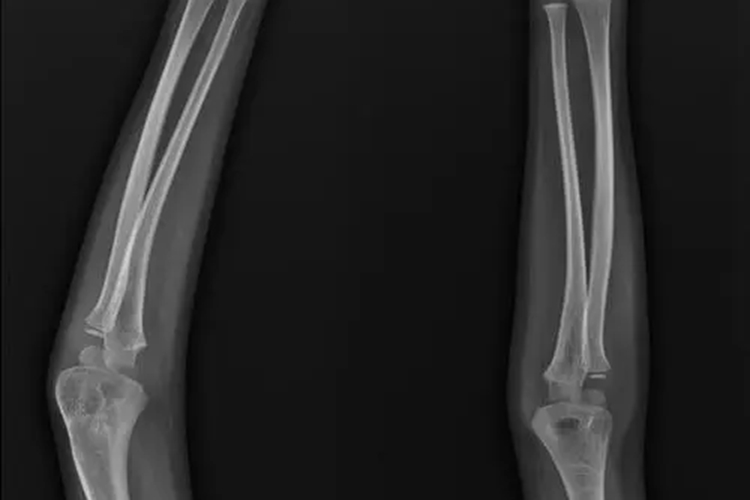

手肘外翻是指前臂呈明显外翻畸形,其前臂提携角(肱骨的纵轴线与尺骨的长轴线在肘部相交所构成一向外开放的钝角)过大,一般大于15°以上。外翻严重时,可有神经分布区域皮肤感觉的迟钝或刺痛、肌萎缩及肌无力的表现。X线检查可见肘关节提携角明显过大。